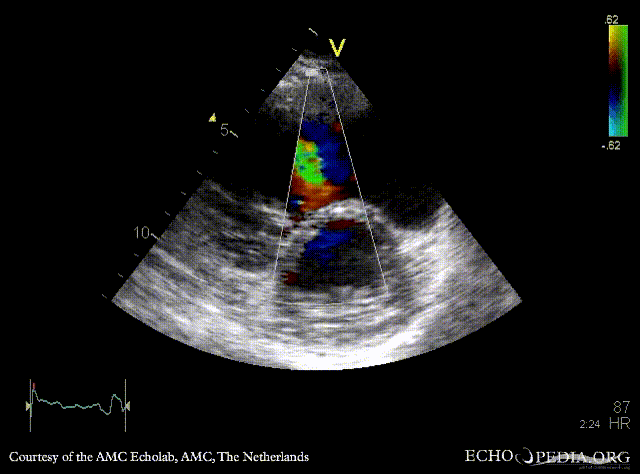

| PSAX: muscular VSD